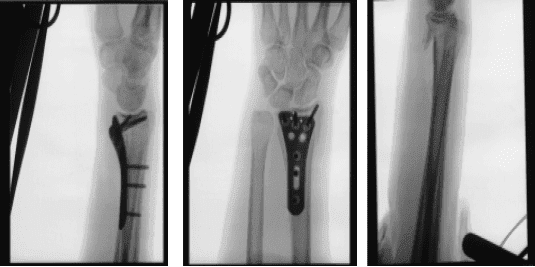

Following a fall, the patient, a 27-year-old female, complains of pain in her right wrist. She has her arm in a brief splint. She underwent a CT scan and x-ray. The distal end of the right side of the radius was found to have a comminuted intra-articular (more than three fragments) fracture after reviewing and discussing the CT and X-ray images.

X-ray wrist 3 or more view

Once the reduction was achieved, Fluoroscopy showed fracture in acceptable position. The plate was put onto the distal radius and held with olive wires. Finding it in acceptable position on fluoroscopy, the plate was fixed distally by the use of a cortical screw, which was later changed to a locking screw.

Once the plate was in good position, fixation of the proximal fragment with the plate was done by the use of three cortical screws. This was followed by fixation of the distal fragment with the use of locking screws. The central screw was removed and wasted and a locking screw was inserted. The fixation was found to be satisfactory. Final pictures were taken and saved.